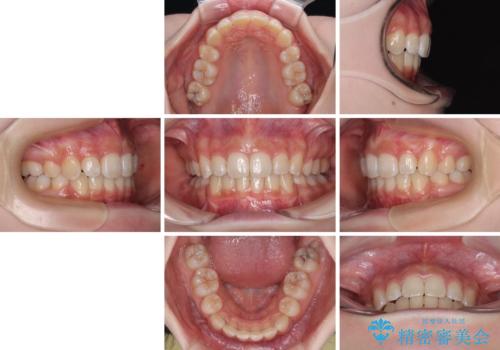

抜歯矯正により、下唇が前方に突出した感覚が大幅に改善されました。